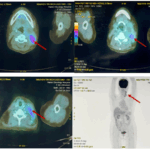

CASE LÂM SÀNG Điều trị bệnh nhân mắc đồng thời hai loại ung thư: Ung thư phổi và ung thư tuyến tiền liệt

CASE LÂM SÀNG Điều trị bệnh nhân mắc đồng thời hai loại ung thư: Ung thư phổi và ung thư...